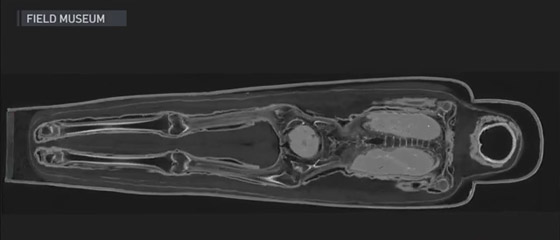

وقام أعضاء فريق العمل في سبتمبر/أيلول، بنقل 26 من المومياوات المعروضة في المتحف على عربات مبنية خصيصًا إلى ساحة ركن السيارات لوضعها عبر ماسح ضوئي متحرك للتصوير المقطعي المحوسب. وأسفرت هذه التكنولوجيا عن الآلاف من الصور الموثقة بالأشعة السينية للمومياوات وتوابيتها.

صور موثقة بالأشعة السينية للمومياوات وتوابيتها

وعند تكديسها معًا، أنشأت المسوحات صورًا ثلاثية الأبعاد كشفت عن الهياكل العظمية والتحف الموجودة بالداخل. ويساهم هذا الأمر في إلقاء الضوء على ممارسات المصريين الجنائزية منذ أكثر من 3 آلاف عام. وقال كبير أمناء علم الأنثروبولجيا في المتحف جيه بي براون إنه بينما استغرق إكمال عمليات المسح أربعة أيام، إلا أنّ معالجة وتحليل النتائج استغرقت ما يصل إلى ثلاث سنوات.

علماء يحلون لغزا عمره 3 آلاف عام عن مومياء امرأة مصرية ذات مكانة عالية صورة رقم 1

علماء يحلون لغزا عمره 3 آلاف عام عن مومياء امرأة مصرية ذات مكانة عالية صورة رقم 2